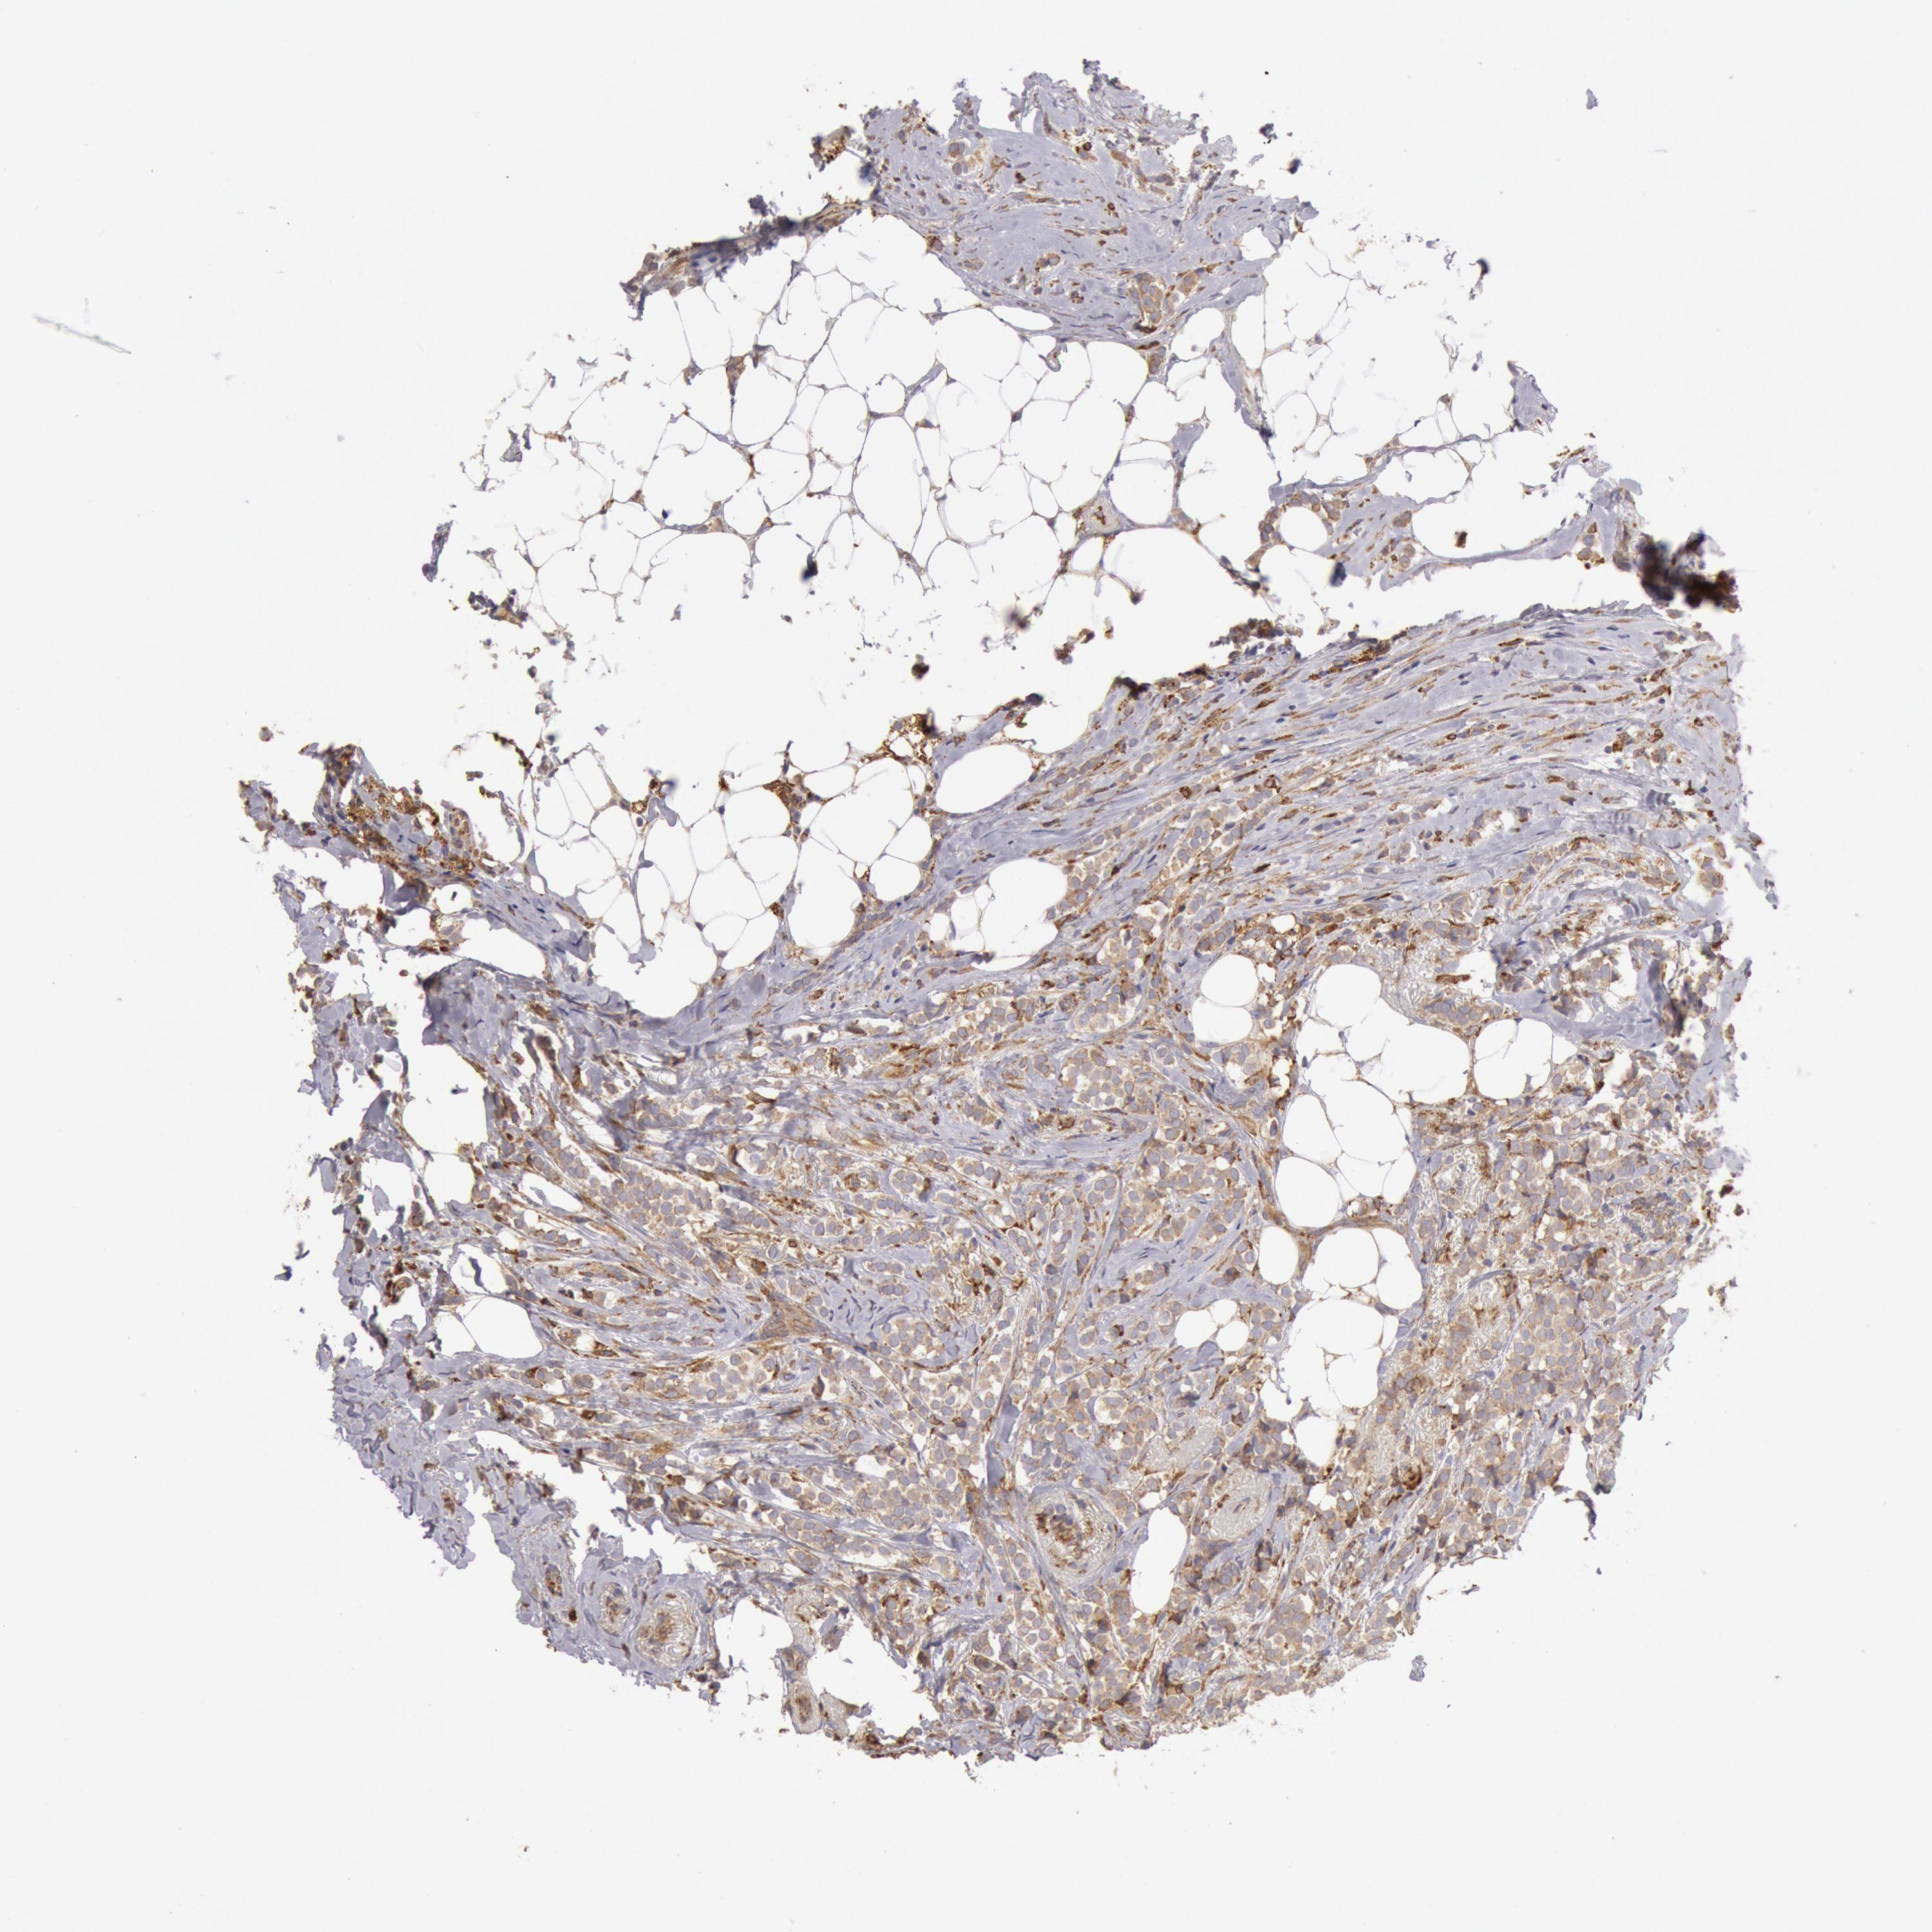

BRCA TCGA BRCA VALIDATION PROTEIN EXPRESSION